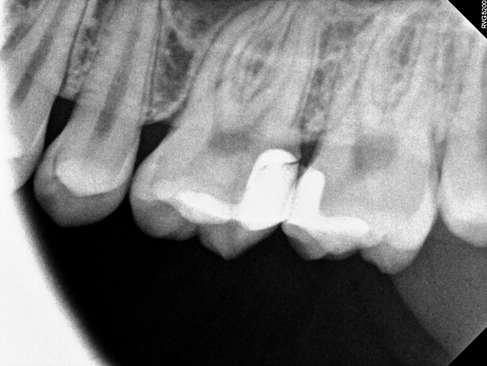

부산충치치료 X-ray 사진 입니다.

치아 사이 면에 검게 충치가 진행되고 있는 것을 확인할 수 있습니다.

충치의 범위가 넓기 때문에 레진으로는 치료할 수 없어 오른쪽 첫 번째, 왼쪽 두 번째 어금니는 하이브리드 인레이(부분보철)로 진행하였습니다.